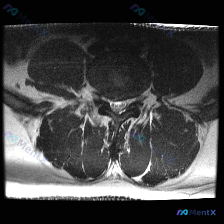

今天整理了一份只有单张腰椎MRI T2加权轴位片的椎间盘病变分析案例,跟大家分享一下读片和临床分析的思路。 病例影像基本信息 本次仅提供单张腰椎MRI T2加权轴位图像,具体读片发现如下: 1. 节段定位:根据椎体、椎弓根和关节突形态判断,该切面位于腰椎,最可能为L4/5或L5/S1水平 2. 椎间...

看到这一份腰椎MRI读片病例,临床怀疑存在椎间盘病变,我们整理一下影像资料和完整分析思路,大家一起讨论。 病例影像资料 本次提供的是腰椎MRI T2序列轴位图像,分析如下: 1. 扫描层面:位于下腰椎节段,可清晰辨认中央的硬膜囊、马尾神经根,以及侧方的关节突关节、椎旁肌肉 2. 核心影像发现: -...

这是一份单张腰椎MRI T2轴位影像的分析病例,核心问题是:临床怀疑椎间盘病变,影像上能看到什么问题?整理了完整的读片和分析思路分享给大家。 一、影像基本信息 本次提供的是腰椎MRI T2序列轴位单一层面图像,定位为腰椎椎间盘层面,我们按结构逐一读片: 1. 骨性结构与韧带:椎体形态、骨皮质连续,无...